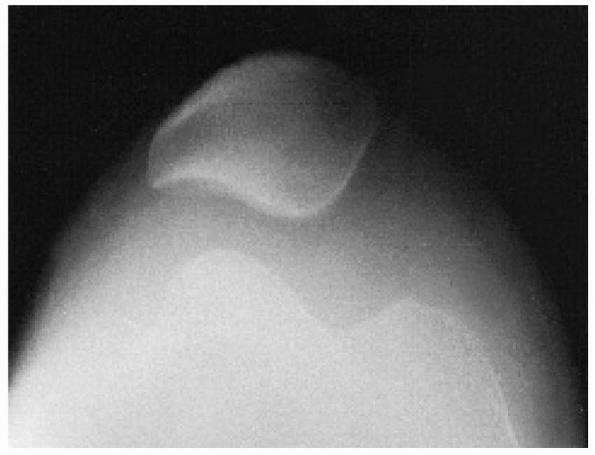

![]() |

|

FIGURE 24-15 Osteochondral fracture of lateral femoral condyle after patellar dislocation. A. Fragment seen in lateral joint space. B. Lateral view.

should begin with anteroposterior, lateral, and skyline plain

radiographs. However, a roentgenographic diagnosis can be difficult

because even a large osteochondral fragment may contain only a small

ossified portion that is visible on plain radiographs. A tunnel view

may help locate a fragment in the region of the intercondylar notch.

Because the osteochondral fragment may be difficult to see on plain

radiographs, radiographs must be carefully assessed for even the

smallest ossified fragment (Fig. 24-15).